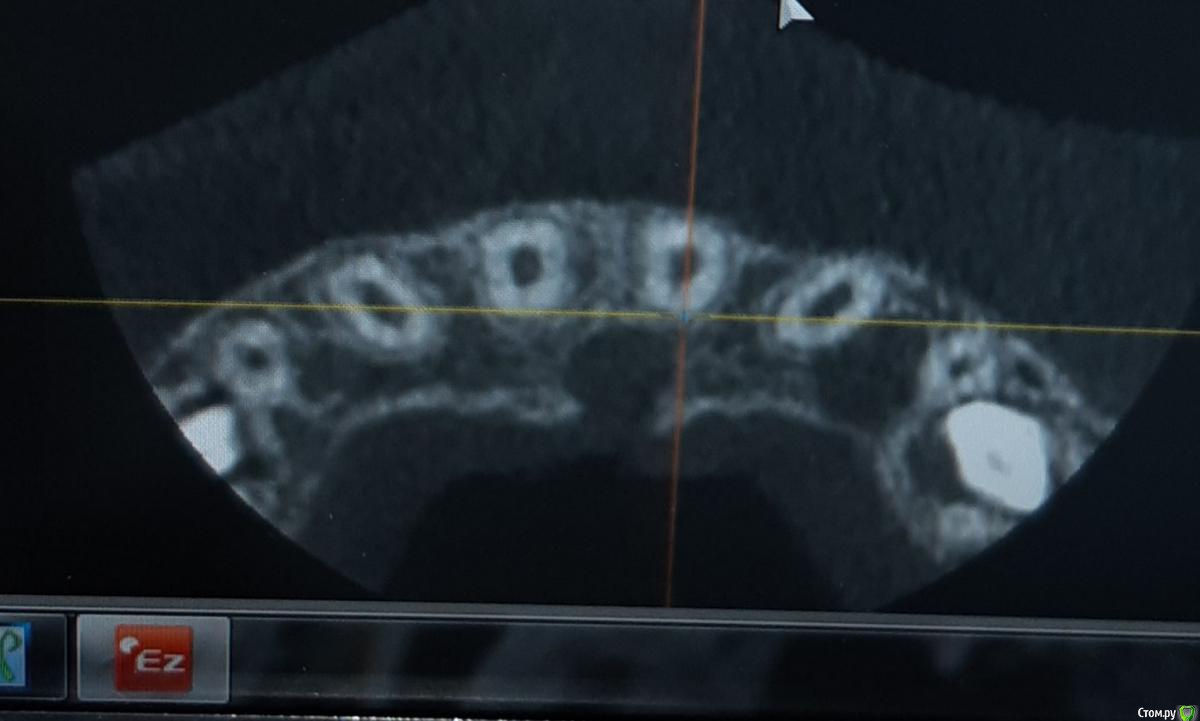

ANCHOUSE Опубликовано 30 марта, 2019 Автор Поделиться Опубликовано 30 марта, 2019 Сделали ктhttps://yadi.sk/d/W9n5FOqj7Rpb4A Ссылка на комментарий

ANCHOUSE Опубликовано 30 марта, 2019 Автор Поделиться Опубликовано 30 марта, 2019 Почему нет кортикалки между 21 и резцовым каналом? Ссылка на комментарий

kramer Опубликовано 30 марта, 2019 Поделиться Опубликовано 30 марта, 2019 Мне кажется, кость рассосалась вследствие возникновения этого новообразования. 1 Ссылка на комментарий

ANCHOUSE Опубликовано 30 марта, 2019 Автор Поделиться Опубликовано 30 марта, 2019 Или от постоянной нагрузки? Ссылка на комментарий

ANCHOUSE Опубликовано 30 марта, 2019 Автор Поделиться Опубликовано 30 марта, 2019 Что имеете ввиду?Сам факт травмы, как раз на эту область Ссылка на комментарий